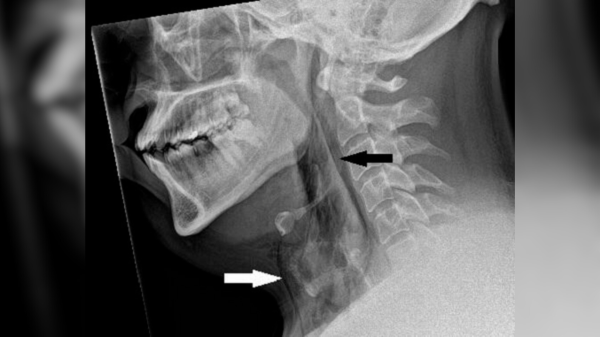

У лікарні рентгенівський знімок верхньої частини хребта чоловіка не виявив жодних відхилень. Однак посилення болю в хребті та скутість шиї спонукали одного з лікарів призначити комп'ютерну томографію (КТ) тієї ж ділянки. На КТ лікарі помітили «клиноподібний, гіперщільний об'єкт», – написали вони у звіті про випадок. Об'єкт проник у задню частину горла чоловіка та увійшов у його спинномозковий канал. Він застряг там, пробивши великий потиличний отвір – великий отвір біля основи черепа, через який проходить спинний мозок.

Діагноз: Лікарі негайно провели чоловікові операцію з видалення прониклого предмета. Вони ввели загальний наркоз, і хірург використав ретрактори — інструменти, що утримують рани відкритими, — щоб оголити предмет, який виявився зламаним кінчиком риб’ячого дзьоба.

Лікування: Гострий фрагмент дзьоба так міцно застряг у черепі чоловіка, що хірургу довелося зробити додатковий розріз над верхнім хребцем чоловіка, щоб видалити його, витягнувши вздовж шляху введення. Його довжина становила близько 3,5 сантиметрів (1,4 дюйма).